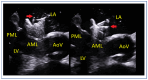

Mitral regurgitation (MR) is a common valvular heart disease associated with significant morbidity and mortality. For patients at high or prohibitive surgical risk, mitral transcatheter edge-to-edge repair (M-TEER) offers a less invasive alternative to surgery. This review outlines key aspects of patient selection and procedural planning for M-TEER, with a focus on clinical and echocardiographic criteria essential for success. Comprehensive imaging-especially 2D and 3D transesophageal echocardiography-is critical to assess leaflet anatomy, coaptation geometry, and mitral valve area. Selection criteria differ between primary and secondary MR and are guided by trials such as COAPT and MITRA-FR. Optimal outcomes rely on careful screening, anatomical suitability, and multidisciplinary evaluation. With growing experience and advancing technology, M-TEER has become a transformative option for treating severe MR in non-surgical candidates.